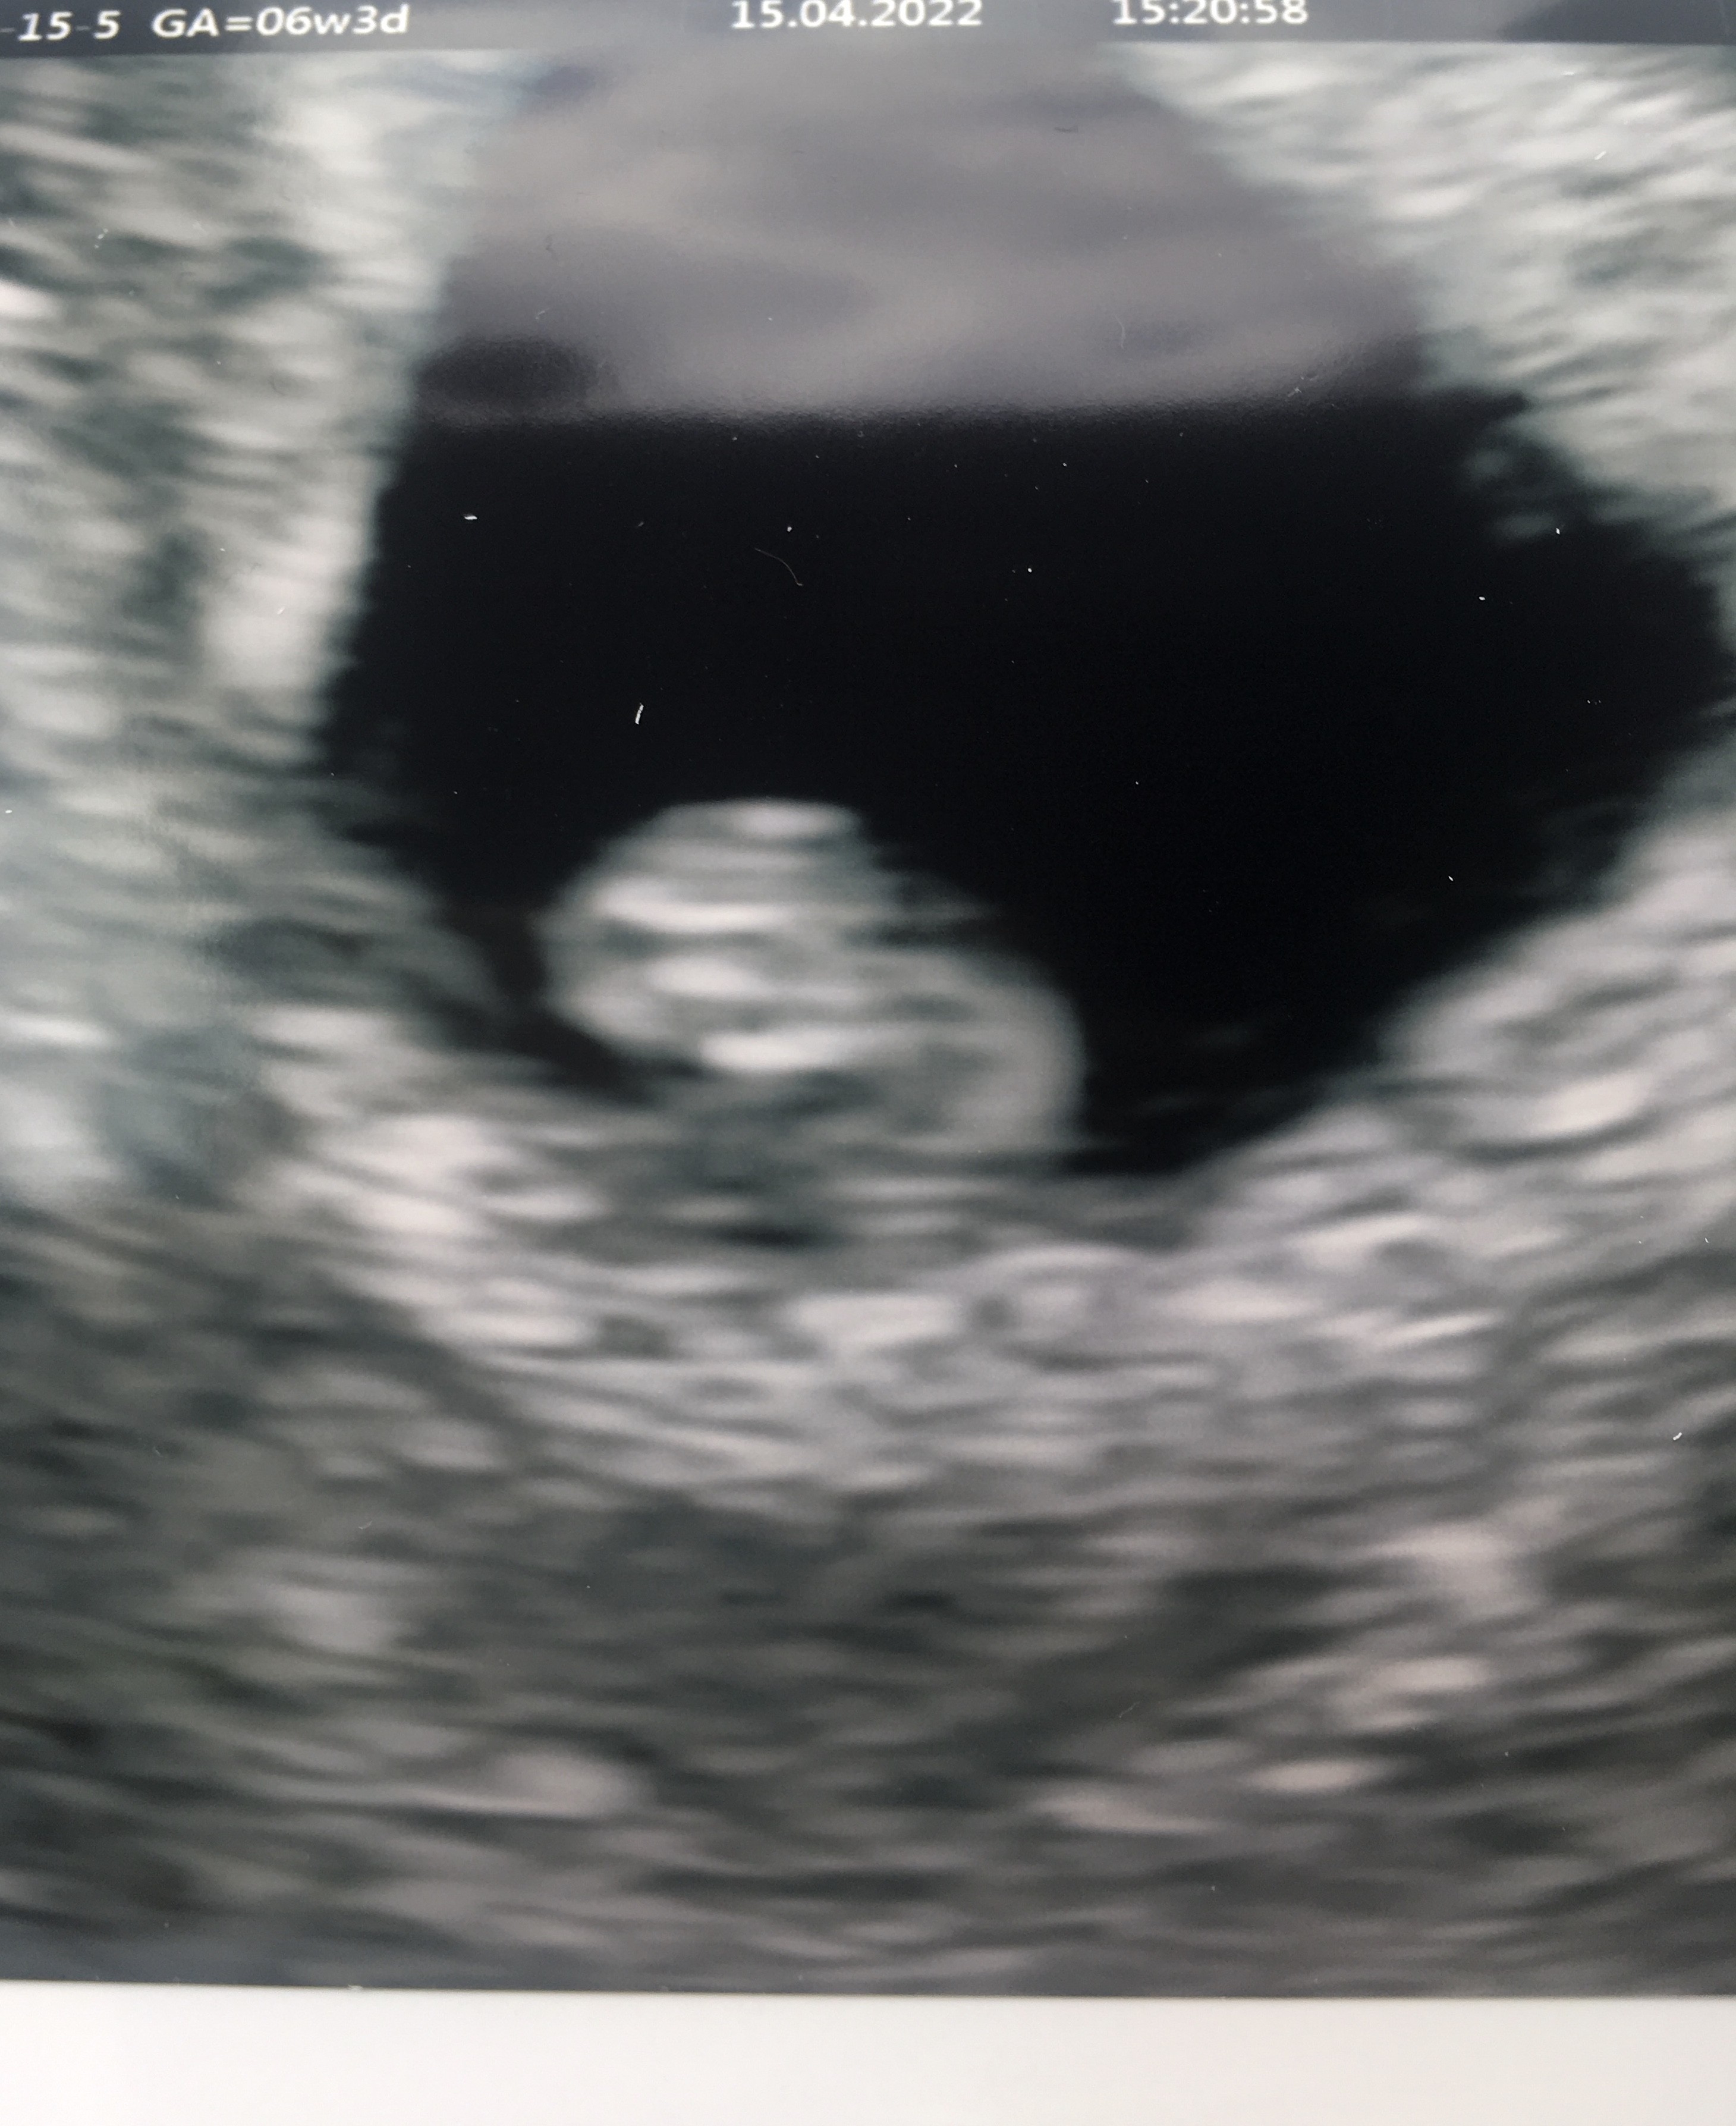

aaaaa! super <3 zdrówka!Dziewczyny poznajcie naszego niedzwiadkaWszystko w idealnym porzadku, serduszko bije!

W poniedziałek 11.04 beta 193,60 a 13.04 - 468,60. Dziś byłam na usg bo bardzo bałam się że znów będzie cp, na szczęście w macicy jest kropka, jest grube endometrium a w jajnikach i jajowodach czysto

I termin wg aplikacji 20.12 czyli święta będą wyjątkowe